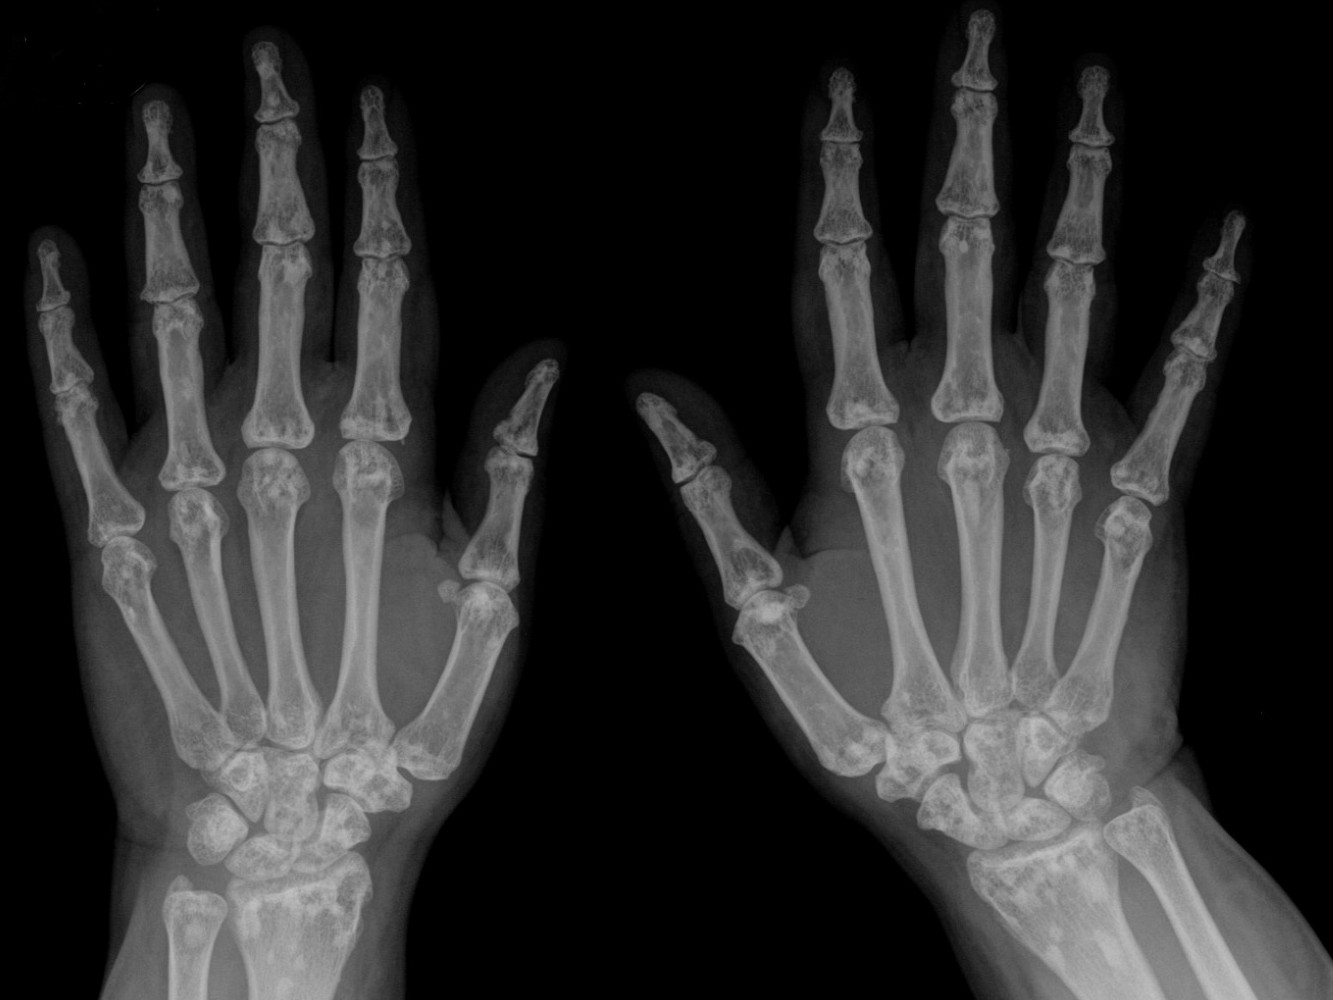

![Elastoma (click on photo to enlarge) [source: www.huidziekten.nl] Elastoma](../../../images/elastoma-1z.jpg) |

![Elastoma (click on photo to enlarge) [source: www.huidziekten.nl] Elastoma](../../../images/elastoma-2z.jpg) |

| elastoma |

elastoma |